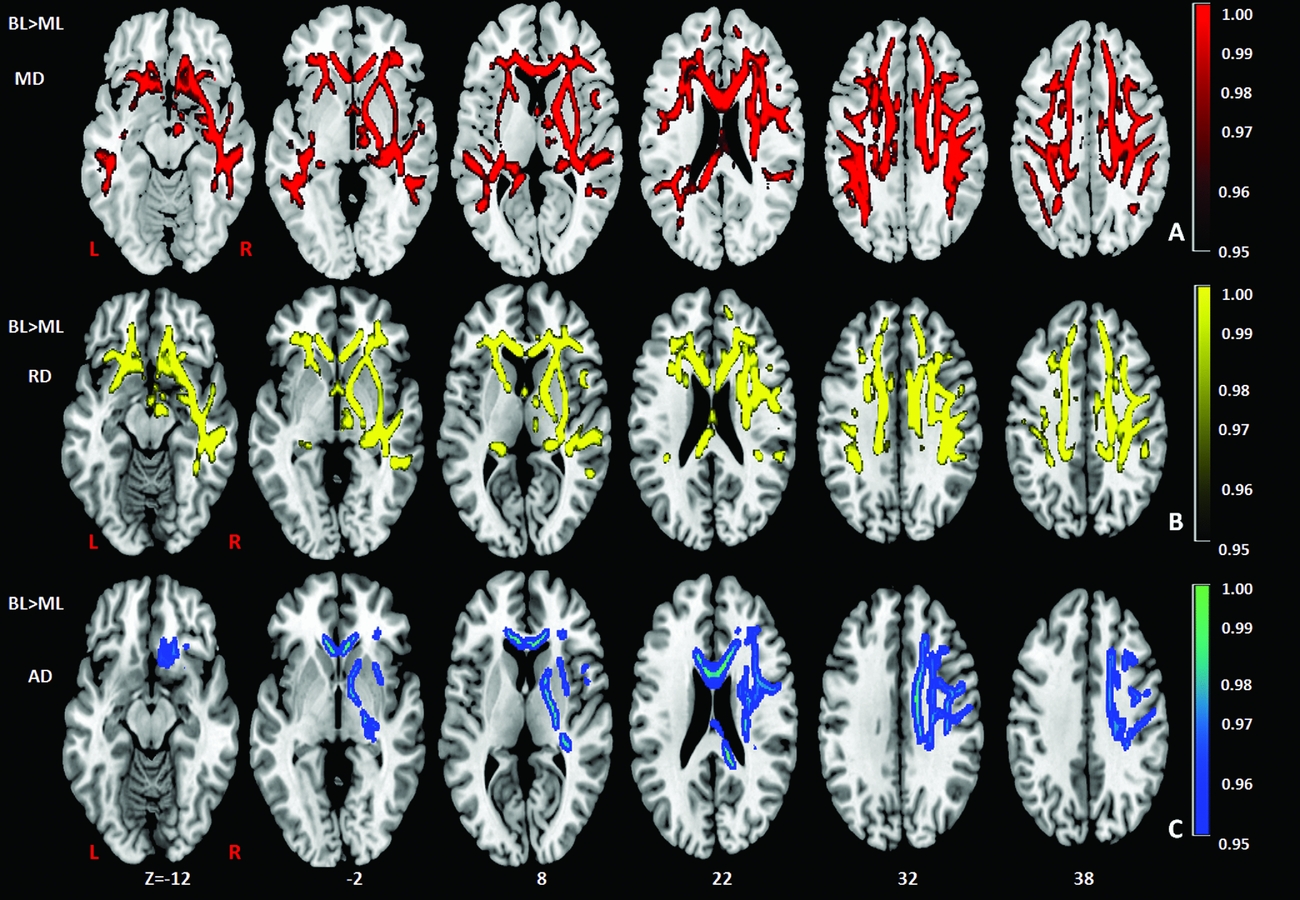

Comparison of the DTI measures between monolingual and bilingual speakers (Monolingual > Bilingual) found reduced mean FA (p<.05) in the right anterior thalamic radiation, ILF and IFOF (Figure 1). Reverse contrasts between bilingual and monolingual speakers (Bilingual > Monolingual) were not significant. TBSS revealed higher mean MD for bilinguals in forceps minor and bilateral SLF (Figure 2, Panel A). Bilinguals also had higher mean RD in forceps minor, right SLF, ILF and the right anterior thalamic radiation (Figure 2, Panel B) and higher mean AD in forceps minor, right SLF and right anterior thalamic radiation (Figure 2, Panel C). Comparisons between monolingual and bilingual speakers (Monolingual > Bilingual) found no significant differences in mean MD, RD or AD (p>0.05). For bilingual speakers, there was a positive correlation (r=0.424) between average L2 proficiency score and mean RD in the right SLF (p<0.07) (see Figures 4 and 5, for details). A summary of the TBSS analyses of regions where mean RD correlated with average L2 proficiency for bilinguals is shown in Figure 4 and Figure 5 shows the plot of mean RD and average L2 proficiency in the right SLF. A component L2 proficiency index was constructed comprising speaking, reading, writing and comprehension scores and it revealed significant correlations between speaking in L2 (p<0.07) and writing in L2 (p<0.05) with mean RD values in right SLF (see Table 5).

Figure 1. TBSS results showing group differences (BL> ML) in mean diffusivity (MD) (red), radial diffusivity (RD) (yellow), axial diffusivity (AD) (blue), expressed in 1-P values (p=0.05, corrected) and overlaid onto MNI152 template. Superior Longitudinal Fasciculus (SLF) and forceps minor (FM) in the right hemisphere have also been indicated. TIV (total intracranial volume) was added as a regressor in the analysis to ensure that differences in TIV between the groups did not contribute to other variables. BL=Bilinguals, ML=Monolinguals.

The results support our expectations that white matter microscopic differences will be found in white matter tracts for bilingual compared to monolingual speakers. We observed higher mean MD, RD and AD for bilingual speakers in forceps minor and right SLF and a positive correlation between L2 proficiency and mean RD in the right SLF. Furthermore, as reported by Cummine and Boliek (Reference Cummine and Boliek2013) with a comparable sample, we confirmed reduced mean FA for bilinguals in the anterior thalamic radiation and the right IFOF. However, unlike Cummine and Boliek (Reference Cummine and Boliek2013) we did not find reduced MD in forceps minor or left IFOF or no evidence of increased MD in the cingulum for bilingual speakers. Other studies using different samples also report differences in mean FA, MD and RD between monolingual and bilingual speakers (Gold et al., Reference Gold, Johnson and Powell2013; Luk et al., Reference Luk, Bialystok, Craik and Grady2011; Kuhl, Richards, Stevenson, Can, Wroblewski, Fish & Mizrahi, Reference Kuhl, Richards, Stevenson, Can, Wroblewski, Fish and Mizrahi2013; Plitsiakis et al., Reference Pliatsikas, Moschopoulou and Saddy2015). However, we show for the first time that mean axial diffusivity (AD) is greater for bilingual than monolingual speakers in forceps minor and right SLF. We note that the same pattern was observed in the right SLF for mean MD and RD and moreover that the right SLF is implicated in neuroplasticity after second language experience (cfr. Qi et al., Reference Qi, Han, Garel, San and Gabrieli2015 discussed below). We discuss the implications of these results for models of bilingual language processing in detail below.

Bilingual adults had higher mean MD values in bilateral SLF and forceps minor, higher mean RD in right SLF, forceps minor and higher mean AD in right SLF and forceps minor. These findings converge on a pattern that reflects the role of language control in bilingual speech in our view. It is of interest that higher mean RD and mean AD in the anterior thalamic radiation are coincident with lower FA in the same region which may indicate a different pattern of myelination. Furthermore, mean FA is in fact lower for bilingual speakers than monolingual speakers. One possible inference is that higher RD and AD, which characterize the rate of diffusion in the perpendicular and parallel directions respectively, indicate a higher rate of isotropic diffusivity in bilinguals but lower axonal density, myelination and coherence in the orientation of white matter as reflected in mean FA. However, although myelination may be reflected in changes to mean axial and radial diffusivities, the underlying mechanisms are complex. Myelination is not a necessary condition for anisotropy and an increase reflects coherent organization of the fibre tracts within the voxel more than myelination per se. Other factors such as the variability in axonal dimensions, membrane permeability, membrane packing density and extra cellular spacing between axons may contribute to mean FA values. Indeed, results from computer simulations suggest axonal diameter and membrane permeability affect transverse (or perpendicular) ADC (Beaulieu, Reference Beaulieu2002). Moreover, unlike

Turning to differential patterns of diffusivity across studies, we begin with the MD findings. MD is a measure of neuroplasticity that is assumed to reflect tissue changes such as astrocyte swelling, synaptic changes, dendritic spine changes and angiogenesis (Takeuchi, Taki, Nouchi, Hashizume, Sekiguchi, Kotozaki & Kawashima, Reference Takeuchi, Taki, Nouchi, Hashizume, Sekiguchi, Kotozaki and Kawashima2014). FA and MD are not necessarily correlated, i.e., reduced FA can be observed with increased MD but indices can also be coincident and MD can be lower or higher across different brain regions (Cummine & Boliek, Reference Cummine and Boliek2013). To recap, we found that bilinguals show higher levels of MD in forceps minor and bilateral SLF. The left SLF is classically associated with language processing across languages (cf. Catani et al., Reference Catani, Jones and Ffytche2005; Hickok & Poeppel, Reference Hickok and Poeppel2004, Reference Hickok and Poeppel2007). The left SLF has been implicated in language production and is associated with the dorsal language pathway (Saur, Kreher, Schnell, Kummerer, Kellmeyer, Vry et al., Reference Saur, Kreher, Schnell, Kummerer, Kellmeyer, Vry and Weiller2008) that connects Broca's area and premotor cortex to the Superior Temporal Gyrus (STG) – all regions that have a role in the articulation of language (Friederici, Reference Friederici2011). We note here that fMRI studies report that practice on non-verbal training tasks (reversing the Simon effect) is negatively correlated with neural activity in right ventral premotor cortex (vPMC) (Wang & Weekes, Reference Wang and Weekes2014). Although classical neurobiological models of language processing assume left hemispheric dominance, the advent of brain imaging data – including specifically in bilingual speakers – revealed bilateral activation (Chee, Caplan, Soon, Sriram, Tan, Thiel & Weekes, Reference Chee, Caplan, Soon, Sriram, Tan, Thiel and Weekes1999; Chee, Weekes, Lee, Soon, Schreiber, Hoon & Chee, Reference Chee, Weekes, Lee, Soon, Schreiber, Hoon and Chee2000; Hämäläinen, Sairanen, Leminen & Lehtonen, Reference Hämäläinen, Sairanen, Leminen and Lehtonen2017; Hull & Vaid, Reference Hull and Vaid2006; Weekes, Coltheart & Gordon, Reference Weekes, Coltheart and Gordon1997) as well as evidence of a shift to the right hemisphere for L2 related tasks (Dehaene, Dupoux, Mehler, Cohen, Paulesu, Perani et al., Reference Dehaene, Dupoux, Mehler, Cohen, Paulesu and Perani1997; Xiang, Leeuwen, Van Dediu, Norris & Hagoort, Reference Xiang, Leeuwen, Van Dediu, Norris and Hagoort2015). Since languages differ in articulatory features, speakers of multiple languages are required to develop a repertoire of articulatory gestures that are unique to a target language. Therefore, speakers of two or more languages have additional needs to coordinate their verbal motor acts when compared to monolinguals. Such gestures are likely supervised by the language control system that adjusts utterances to context and eschews utterances from a non-target language (Abutalebi & Green, Reference Abutalebi and Green2007; Abutalebi, Reference Abutalebi2008). Such control of the language system is achieved through a bilateral network of brain areas related to cognitive control including prefrontal areas, ACC, parietal areas and the caudate nucleus (Abutalebi & Green, Reference Abutalebi and Green2016). Evidence of DTI changes in the right hemisphere reported here may be specifically related to language control processes necessary to support L2 processing. Our results show a bilateral pattern of white matter changes measures detected through MD for bilingual speakers, in regions of the right hemisphere that coincides with RD and AD. In the light of these findings, we suggest that the changes in tract geometry in the right SLF for the present sample reflect early immersion and daily use of L2.

We found little evidence that left hemisphere networks and tracts become more important as language proficiency improves at least when the language is early acquired and used daily. It is also notable that studies with simultaneous interpreters compared to matched monolingual controls report decreases in FA at the whole brain level that accompany increases in RD and decreases in AD in the CC, the cortico-spinal tract and cingulum bundle (Elmer, Hanggi, Meyer & Jancke, Reference Elmer, Hanggi, Meyer and Jancke2011). Differences were attributed to demands in sensory-motor coupling mechanisms necessary for simultaneous interpreters in regions supporting articulation such as forceps minor (Figure 1).